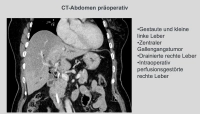

No caso demonstrado, trata-se de um tumor estenosante do ducto biliar na bifurcação hepática Bismuth IIIb, diagnosticado por MRCP, ERCP e citologia por escova. Uma ressecção direita estendida não era viável devido à atrofia do lobo hepático esquerdo. Portanto, foi realizada a remoção dos segmentos hepáticos 1, 4, 5 e 8, preservando os segmentos laterais 6, 7 e 2, 3, particularmente porque a bifurcação da veia porta e a artéria hepática esquerda não pareciam infiltradas morfologicamente.